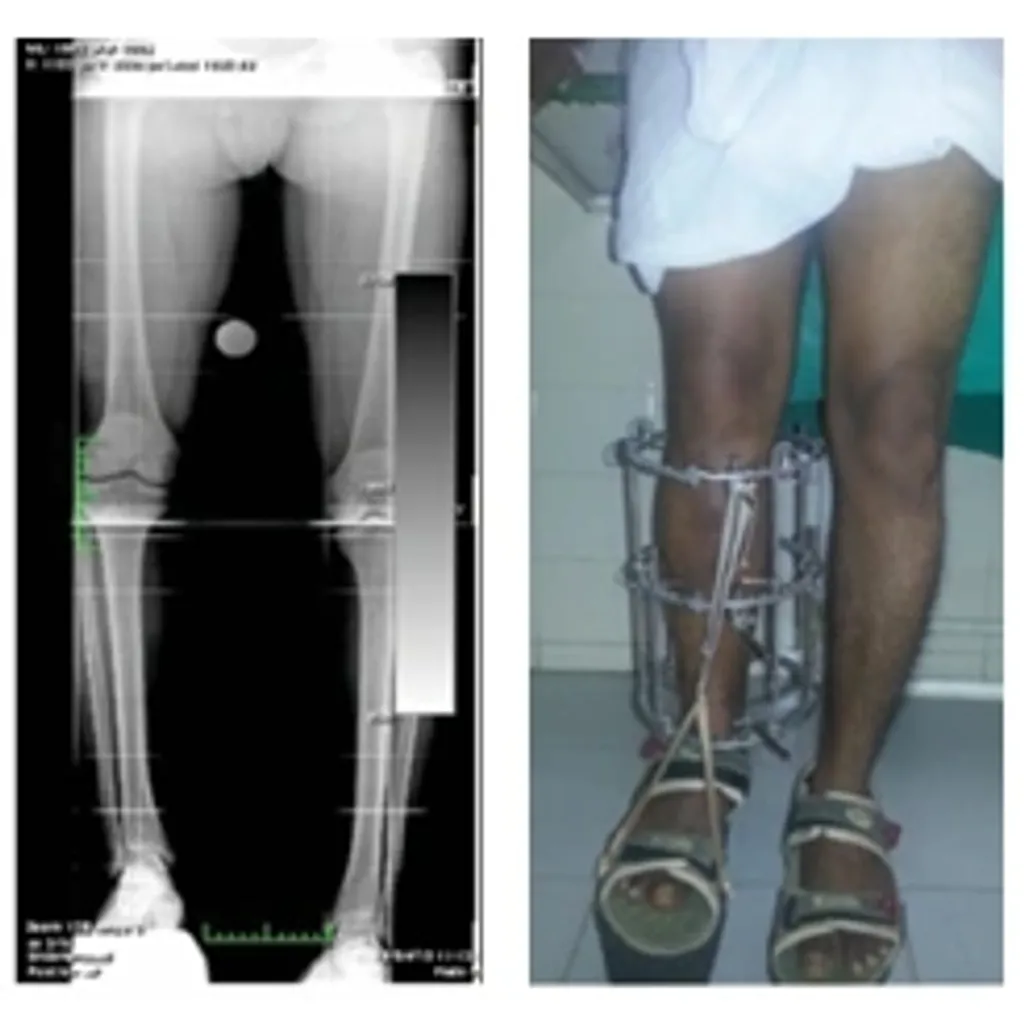

മൂന്നാമത്തെ ഉദാഹരണം 45 വയസ്സുള്ള ഒരു സ്ത്രീയുടേതാണ്. അവൾ വൈകല്യ സർട്ടിഫിക്കറ്റ് ലഭിക്കുന്നതിനായി ഡിസബിലിറ്റി ബോർഡിൽ എത്തിയതായിരുന്നു. തന്റെ വൈകല്യം ശാശ്വതമാണെന്നും ചികിത്സയിലൂടെ ശരിയാക്കാനാകില്ലെന്നും അവൾ കരുതിയിരുന്നു.

കുട്ടിക്കാലം മുതൽ തന്നെ ഉണ്ടായിരുന്ന, പക്ഷേ അവഗണിക്കപ്പെട്ട CTEV (ക്ലബ് ഫൂട്ട്) പ്രശ്നമാണ് അവൾക്കുണ്ടായിരുന്നത് (Fig 13 a,b,c). ഇതുമൂലം നടക്കാൻ ബുദ്ധിമുട്ടും വേദനയും അനുഭവപ്പെട്ടിരുന്നു.

ഇലിസാരോവ് ചികിത്സയിലൂടെ ഇത് പരിഹരിക്കാനാകുമെന്ന് വിശദമായി അവൾക്ക് വിശദീകരിച്ചു. ആദ്യം ശസ്ത്രക്രിയയ്ക്ക് അവൾ മടിച്ചെങ്കിലും, വിശദമായ ബോധവൽക്കരണത്തിന് ശേഷം ചികിത്സയ്ക്ക് സമ്മതിച്ചു. ഈ രീതിയിൽ കാൽഭാഗത്ത് തുറന്ന ശസ്ത്രക്രിയ വേണ്ടതില്ലാത്തതിനാൽ, ഫ്ലാപ്പ് നെക്രോസിസ്, ഫൂട്ട് കമ്പാർട്ട്മെന്റ് സിന്‍ഡ്രോം തുടങ്ങിയ സങ്കീർണ്ണതകൾക്ക് സാധ്യത വളരെ കുറവാണ്.

ഇലിസാരോവ് ഫ്രെയിം ഘടിപ്പിച്ച് ക്രമാനുസൃത പരിഹാരം നടത്തിയതോടെ, അവളുടെ കാൽ വൈകല്യം വിജയകരമായി ശരിയായി (Fig 14 a,b,c,d,).